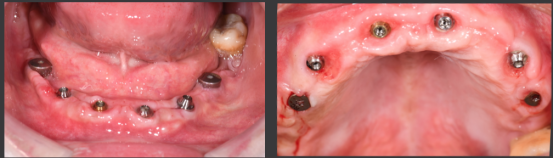

下颌即刻种植即刻修复手术过程

· 下颌士卓曼360数字化序列导板+预成临时修复体

· 翻瓣,利用松牙固定后的余留牙支持连接在一起的牙支持导板和基部导板,使骨支持的基部导板就位于骨面。

· 并用固位钉固定,拆除牙支持式导板,拔除余留牙。

· 基部导板上缘做为截骨线,精确去骨,平整骨面。

· 全程植入导板就位于基部导板上,固位钉固定,引导种植体植入。

· 种植体植入后,安装复合基台基底

· 临时修复体就位于基部导板,固位钉固定,口内Pick-up后取下修改,戴回口内,咬合关系良好。

上颌即刻种植即刻修复手术过程

· 上颌360数字化序列导板+预成临时修复体

· 拔除部分牙齿,翻瓣,利用剩余牙齿支持组合导板,辅助基部导板就位固定,基部导板上缘做为去骨线,精确去骨。

· 拔除部分牙齿,翻瓣,利用剩余牙齿支持组合导板,辅助基部导板就位固定,基部导板上缘做为去骨线,精确去骨。

· 全程导板就位,引导种植体植入,安装复合基台。

· 种植体植入位置偏腭侧,唇侧骨量过于丰满,上颌骨前突,去骨修整骨边缘。

· 口内pick-up 固定临时修复体,患者上下颌咬合关系良好。